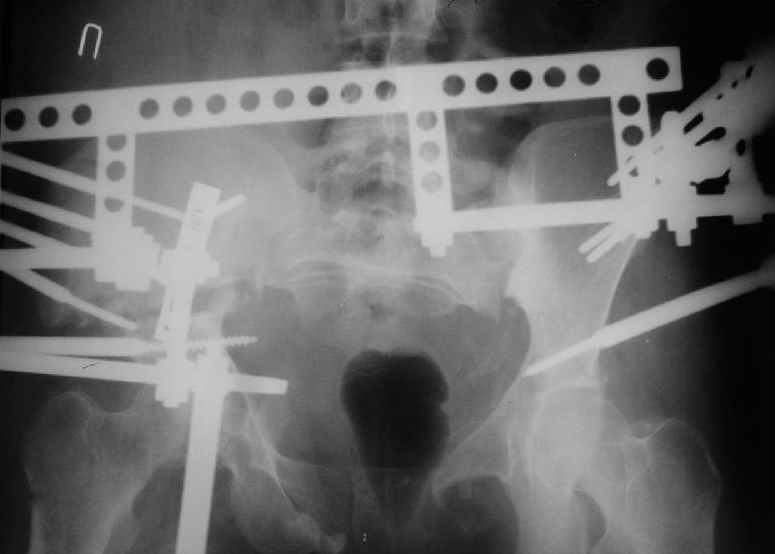

Уважаемые коллеги, вашему вниманию предлагается продолжеие истории лечения больной с двусторонней деформацией таза . Итак, 26.01.05 была выполнена остеотомия правой подвздошной кости, низведение правой вертлужной области, остеосинтез правой подвздошной кости пластиной, чрескостный остеосинтез аппаратом таз-бедро.  Снимок после первого этапа | После заживления раны и стабилизации общего состояния 22.02.05 была выполнена реконструкция переднего отдела таза, синтез лонных костей пластиной, опора с бедра демонтирована, выполнено введение илиосакральных винтов с обеих сторон. В настоящее время рана зажила первичным натяжением, больная ходит с двумя костылями без опоры на правую нижнюю конечность. С интересом ждем ваши комментарии.